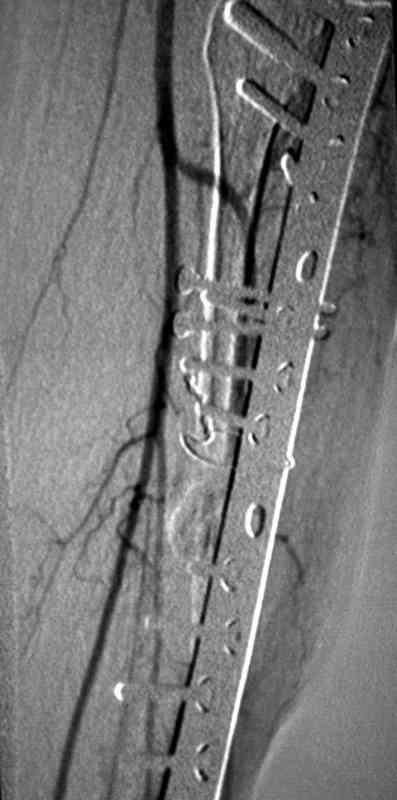

Вторым этапом можно приступить к восстановлению на кости, это может быть сделано аппаратом Илизарова с иссечением концов костей с дальнейшими удлинениями или доступными интра, экстра-медуллярными методами. У нас тоже похожий случай, коллега пластический хирург помог мне, больной после 13 операций на голени,

инфицированный с металлоконструкцией ложный сустав

ангиография,

взятие вены сафенус и подключение к popliteal artery,

rectus muscular flap

вид в аппарате

и окончательный вид.

Для решения проблемы, иногда полезно подтягивания коллег из смежных профессии.